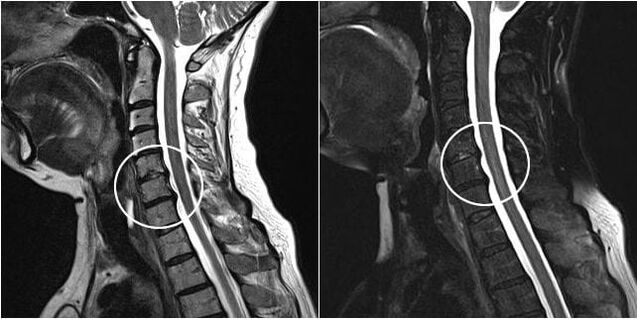

chirurgischer Eingriff

Zu den Indikationen für einen chirurgischen Eingriff zählen die Unwirksamkeit einer konservativen Behandlung sowie Komplikationen der zervikalen Osteochondrose, beispielsweise diskogene Myelopathie, Wirbelarteriensyndrom und radikuläres Syndrom. Um das Rückenmark, die Blutgefäße und die Wirbelsäulenwurzeln zu entlasten, werden folgende Operationen durchgeführt:

Bei der Operation können Knochen- und Bänderfragmente sowie Bandscheiben ganz oder teilweise entfernt werden. Bei kleinen Hernienvorsprüngen wird häufig eine Laserverdampfung des Bandscheibenkerns durchgeführt.

Nach der Entfernung von Wirbelstrukturen ist häufig eine Stabilisierung der Bewegungssegmente der Wirbelsäule durch Wirbelsäulenversteifung oder die Installation von Knochen- und Hautautotransplantaten erforderlich.